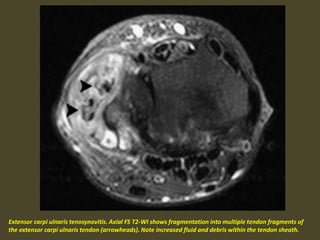

Tenosynovitis of Extensor Carpi Ulnaris.

Extensor carpi ulnaris tenosynovitis. Axial FS T2-WI shows fragmentation into multiple tendon fragments of

the extensor carpi ulnaris tendon (arrowheads). Note increased fluid and debris within the tendon sheath.